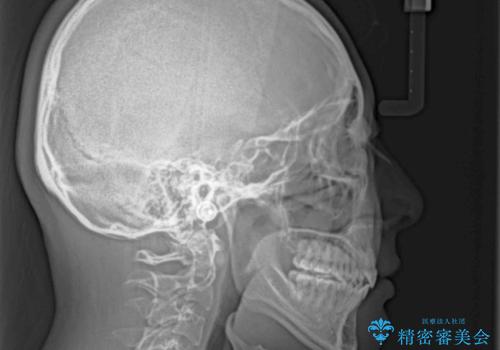

補助装置を併用したおかげでスムーズに奥歯の咬み合わせを改善することができ、我々も予想できないくらい理想的な仕上がりにすることができました。